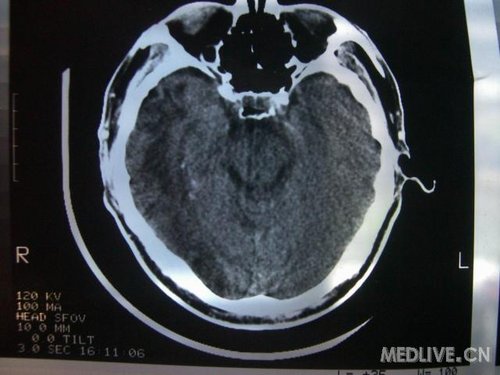

病人男性 73岁 市民 以“幻听、幻视两天,言语含糊、精神错乱一天”入院。

两天前无诱因出现幻听、幻视,描素眼前有彩色的圆圈,听见有人说话(但说什么不详),一天前出现胡言乱语,言语含糊,精神错乱,问话不答,行走略有不稳,来我院就诊,门诊头CT检查:(下面有片)入院后查体不合作,表情淡漠,问话不答,大致检查了一下,颅神经未见明显异常,颈软,右手活动似忽略差。其他检查不配合。脑电图:广泛轻-中度异常。

既往史:半年前曾患“右侧脑梗塞”但无明显后遗症,生活能自理,无高血压、糖尿病、心脏病史。

先传半年前的片子:

此次入院时的片子: